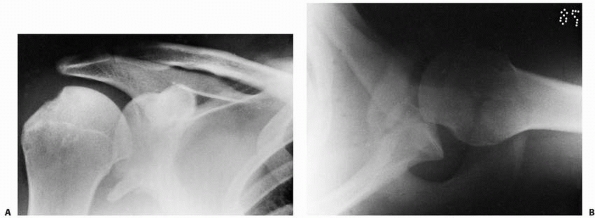

middle third clavicular fractures include severely displaced and

irreducible fractures that threaten skin integrity, concomitant

vascular injury requiring repair, irreducible compression of the

subclavian vessels, compromise of the brachial plexus, and open

fractures.252,267,396,439,598

However, a prospective, randomized study reported that operatively

treated adult clavicle fractures had improved functional outcomes,

decreased time to union, and fewer symptomatic malunions and nonunions

than those treated nonoperatively with a sling.84

While the patients treated operatively also had more hardware-related

complications, the study supported primary plate fixation of midshaft

clavicle fractures in adults. Therefore, internal fixation can be

offered to active, skeletally mature adolescents and young adults with

displaced diaphyseal clavicle fractures (Fig. 17-8).

FIGURE 17-8 A. Radiograph of displaced midshaft clavicle fracture of the dominant upper extremity of a throwing athlete. B. Surgical fixation was performed with a contoured plate and screws.